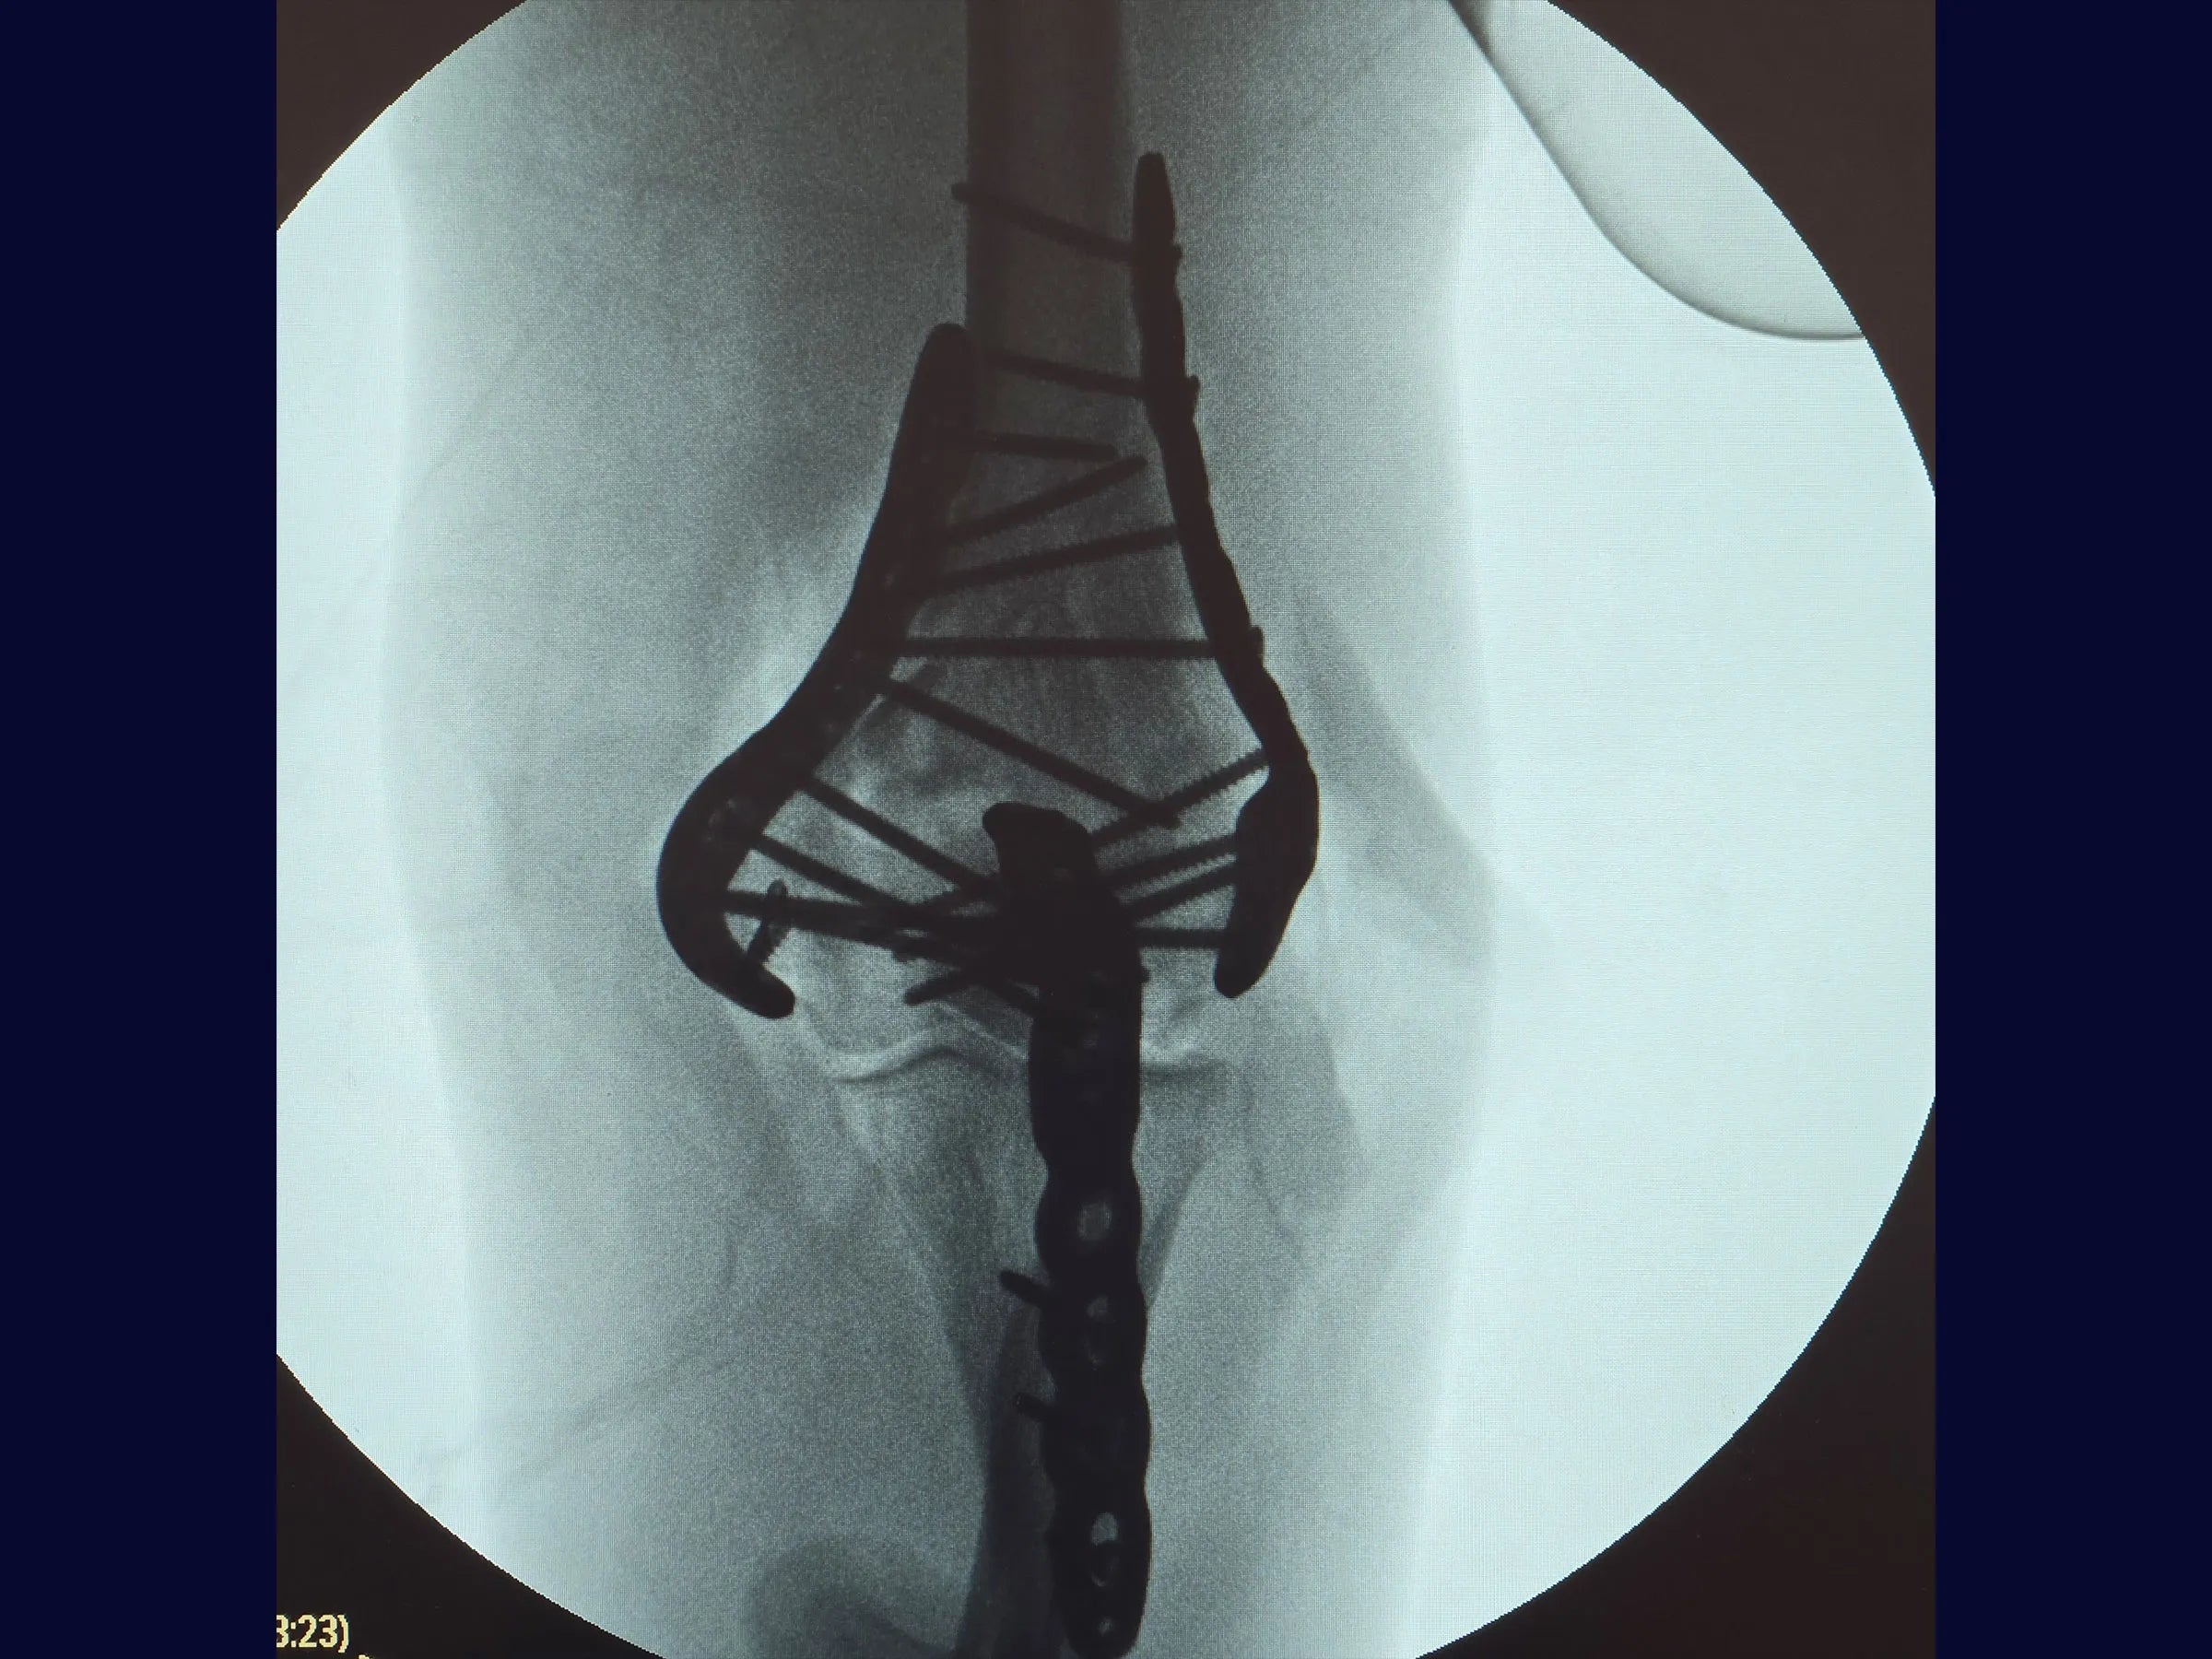

- Osteotomia em Chevron no olécrano para ampla exposição articular.

- Redução de fragmentos articulares com fios de Kirschner em joystick.

- Fixação definitiva com placas bloqueadas de ângulo variável.

- Osteotomia Precisa: Chevron no olécrano com preservação da cartilagem, garantindo estabilidade e preservação anatômica na reconstrução.

- Redução Controlada: Uso de fios K como joystick para manipulação de fragmentos articulares e restauração das colunas.

- Fixação Estável: Aplicação de placas bloqueadas de ângulo variável para alinhamento seguro e resistência biomecânica.